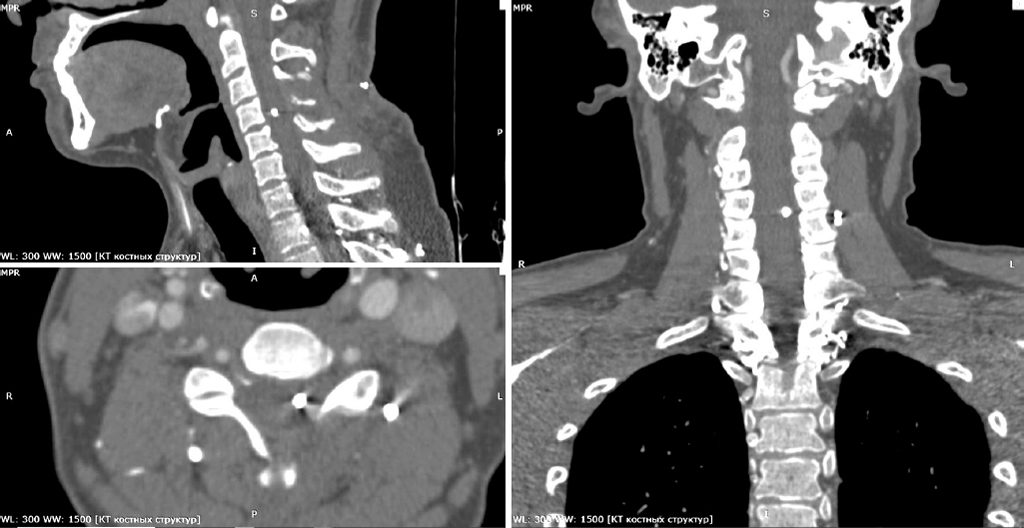

Clinical Case 1: a 63-year-old man with a mine-blast injury and shrapnel gunshot wounds to the head, neck, chest, abdomen, and extremities:

- Comminuted gunshot fractures of the right transverse and superior articular processes of the C6 vertebra and inferior articular process of the C5 vertebra;

- Floating thrombus of the right common carotid artery (Figs. 3 and 4);

- Ischemic stroke in the territory of the right middle cerebral artery (from the time of injury) due to arterioarterial embolism, with development of left-sided hemiparesis and left homonymous hemianopia (Fig. 5);

- Asymptomatic traumatic occlusion of the right vertebral artery;

- Multiple metallic foreign bodies in the soft tissues of the head and neck (including the wall of the right common carotid artery), chest, and extremities.

Fig. 3. Duplex ultrasonography of the cervical vessels. Foreign bodies (fragments and markers 1 and 2) adjacent to the posterior wall of the right common carotid artery. Floating intraluminal thrombus of the posterolateral wall of the middle third of the right common carotid artery (markers 3 and 4). Nonstenotic carotid atherosclerosis.

Fig. 6. Computed tomography of the neck. Postoperative (decompressive interlaminectomy) defect of the left C4 and C5 vertebral arches. Metallic foreign body (3 × 4 mm) projected within the spinal cord. Two metallic foreign bodies in the paravertebral soft tissues at the level of the C5 vertebra.